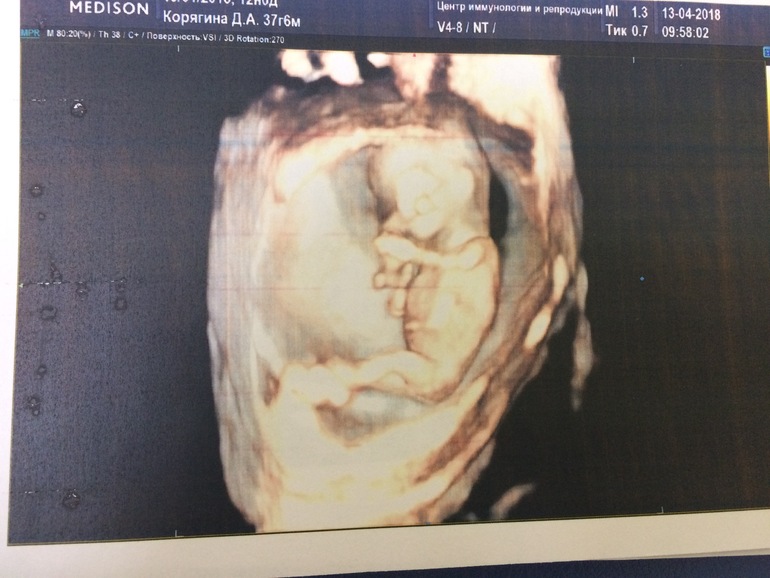

Скининг первого триместра, цир Тё

Те классный, профессионал! Была у него на скрининге почти 9 лет назад:)) Фото просто замечательное, так все хорошо видно:)))

Ага)) я не ожидала даже, что и 3д)